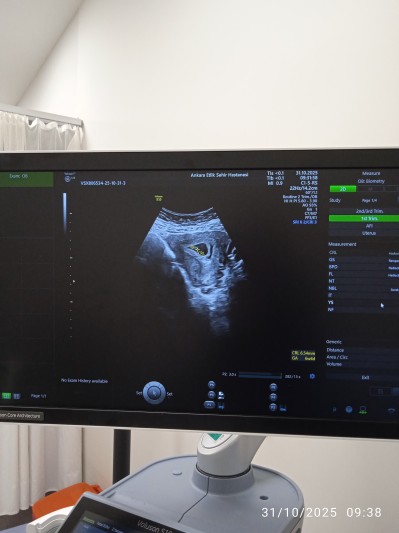

6+5haftalik hamileyim bugün ilk gittim hastaneye kalp atışı başlamış ama kanama alanı var dedi ne yapabilirim

Gebelik haftası 6+5